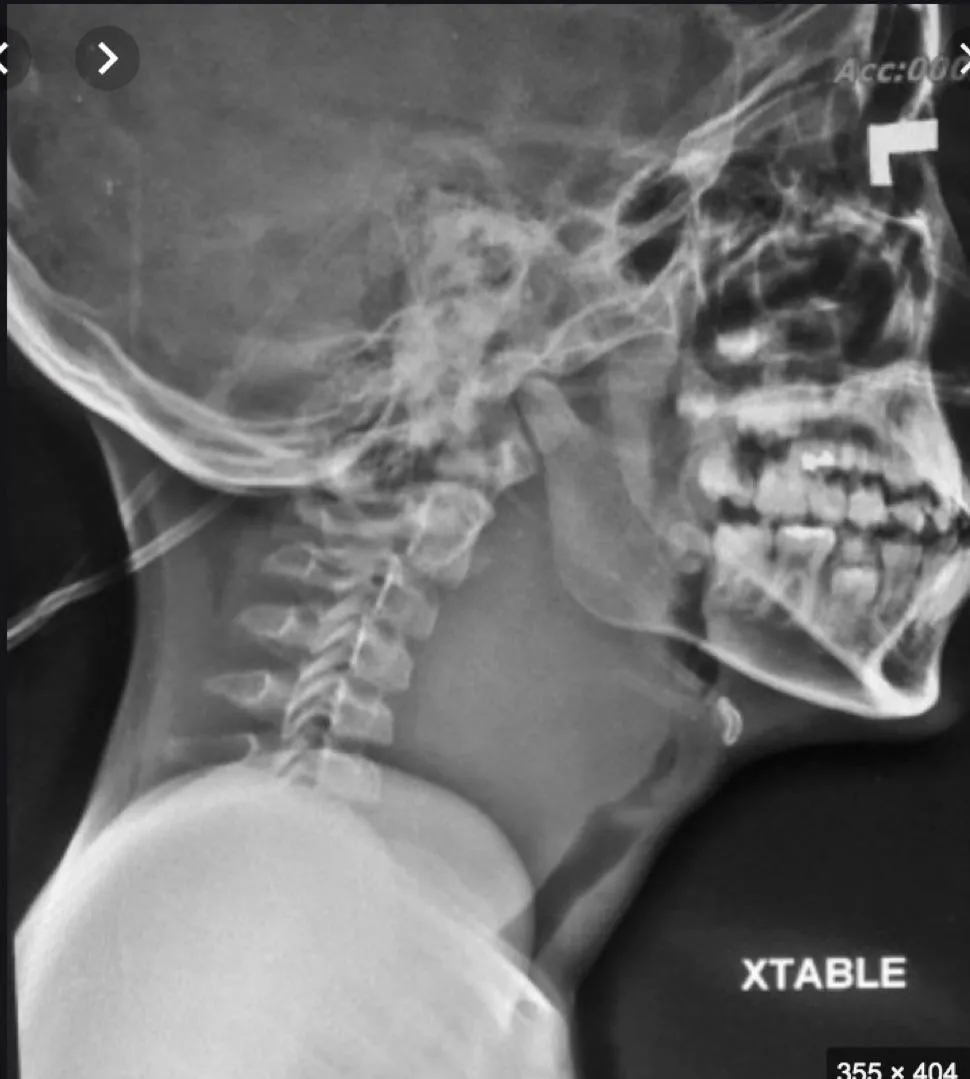

Epiglottitis

A 2-year-old unvaccinated child presented with a 6-hour history of high-grade fever, drooling, and odynophagia. The child appeared ill and irritable with inspiratory stridor. - Diagnosis: Epiglottitis. - Characteristic Sign on Neck X-ray: Thumb sign.

- : A 5-year-old child presented with fever and respiratory distress.

- Diagnosis: Acute epiglottitis.

- Management:

- Dont Examine the child in the OR.

- Intubation.

- IV antibiotics.

- Corticosteroids.

- Sign on X-ray: Thumbprint sign.